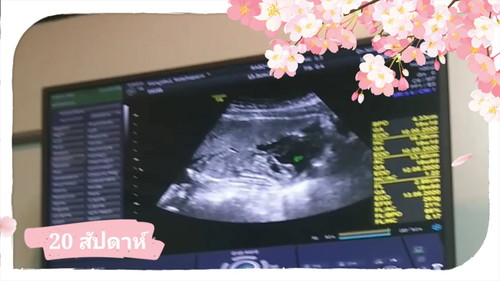

มีอะไรหลายๆอย่างเปลี่ยนไปจากตัวเราไม่ใช่ตัวของลูกและคุณแม่นะครับผมเข้าใจเลยครับว่าคนที่กำลังจะมีลูกเขารู้สึกอย่างไรวันนี้ผมมาทำงานที่กรุงเทพฯประมาณ 2 3 วันต้องห่างลูก ตอนเดินทางขึ้นเครื่อง ว่าเป็นห่วงแล้วนะครับแต่พอมาถึงที่กรุงเทพฯรู้ว่าจะกลับไปเจอเขาอีกทีวันอาทิตย์ยิ่งเป็นห่วงเข้าไปใหญ่ความรู้สึกของคนเป็นพ่อมันน่าจะเริ่มคืบคลานเข้ามาในความรู้สึกของเราแล้วล่ะครับ ลองเป็นพ่อดูนะครับคุณจะเข้าใจความรู้สึกเดียวกับผม